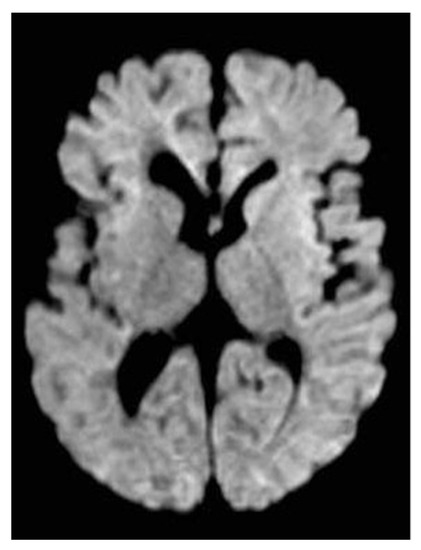

2. Case Description